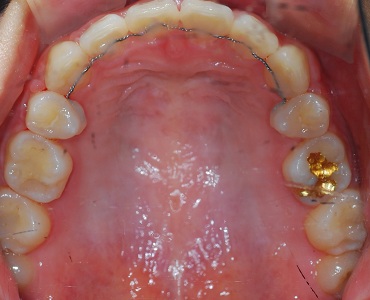

상악을 먼저 치아를 정리한 뒤 본을 뜨고, 하악 치아를 정리하는 사이!

상악의 임시 유지장치가 만들어져요

상악사진